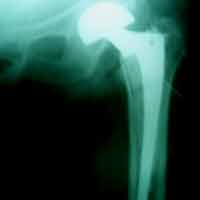

Case:7 Fracture Neck Femur with Implant failure and Re-Fixation with hemi-arthroplasty

Alcoholic Gardener by profession had slipped in bathroom & fell. He sustained fracture neck femur.He was operated with closed reduction & CC Screw fixation under IITV. Two weeks’ post fixation he again fell & sustained fracture in sub trochanteric region. He was treated with Hem-Arthroplasty with Tension band wiring.

Pre-Op

Post-Op

Post Fall

Oblique-Post Fall

Lat-Post Fall

Lateral-Post Prosthesis Fall

Post Prosthesis Fall

Post Uninon-3Months